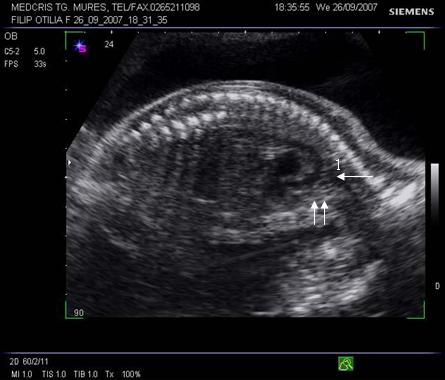

Fig. nr.176. Planul 0 de sectiune transversala ptr examinarea cordului, se incepe cu abdomenul , in care se remarca stomacul si aorta ( cu o sageata ) alaturi spre dreapta , vena cava inferioara ( cu doua sageti )